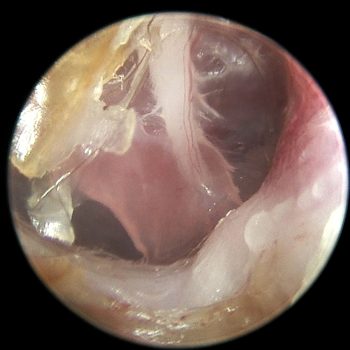

Diagnostyka endoskopowa zewnętrznych przewodów słuchowych (Otoendoskopia)

Głębokie płukanie przewodów słuchowych w znieczuleniu ogólnym

Myringotomia (nakłucie błony bębenkowej z oczyszczeniem z wydzieliny zapalnej) w celu diagnostyki i leczenia zapalenia ucha środkowego i wewnętrznego

Usuwanie ciał obcych (kłosy, bezoary)

Pobieranie biopsji tkanek zmienionych

Resekcję zmian nowotworowych w obrębie ucha zewnętrznego, także przy użyciu lasera